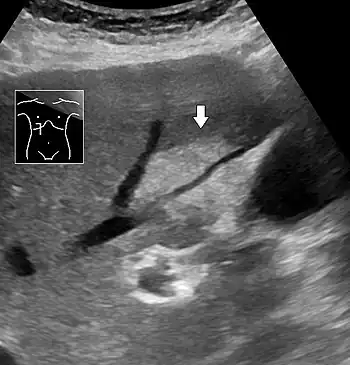

On X-ray computed tomography (CT), the increased fat component will decrease the density of the liver tissue, making the image less bright. Typically the density of the spleen and liver are roughly equivalent. In steatosis, there is a difference between the density and brightness of the two organs, with the liver appearing darker.[12] On ultrasound, fat is more echogenic (capable of reflecting sound waves). The combination of liver steatosis being dark on CT and bright on ultrasound is sometimes known as the flip flop sign.

Abdominal ultrasonography of focal steatosis. It is distinguished from a tumor by not compressing the hepatic vein.